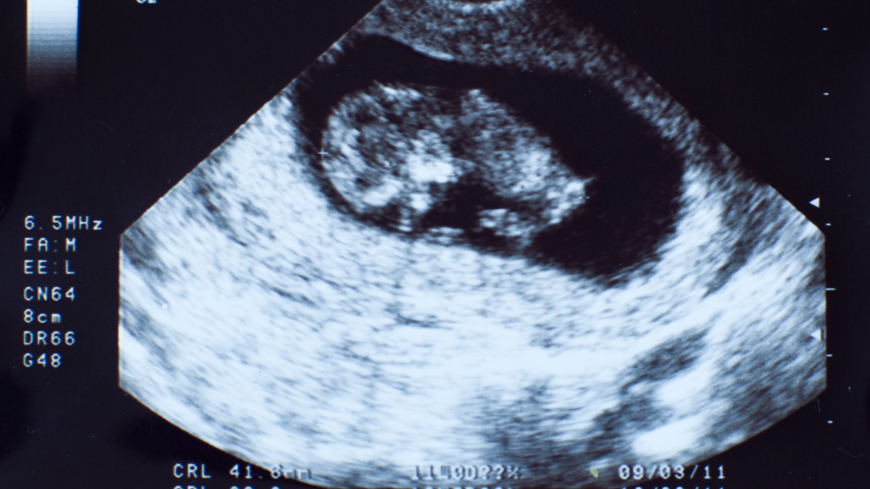

KUB-undersökning vid graviditet

KUB är en förkortning för kombinerat ultraljud och biokemisk screening. Undersökningen görs i graviditetsvecka 11-14. Genom att kombinera ultraljudsundersökningen med ett blodprov och dessutom räkna in mammans ålder, kan man beräkna risken om fostret har Downs syndrom och vissa andra mer sällsynta kromosomavvikelser.

Först tas ett blodprov (biokemisk screening), efter fem dagar görs ett NUPP-test det vill säga en ultraljudsundersökning som används för att mäta en vätskespalt (nackuppklarning) som fostret har i nackgropen. Ju bredare vätskespalten är desto större är risken för att fostret har Downs syndrom. Undersökningen kan bara göras i graviditetsvecka 11-14 eftersom vätskespalten försvinner senare under graviditeten.

Vad kan man se vid en KUB-undersökning?

Med hjälp av ultraljudsundersökning kan man bedöma om det finns en större eller mindre risk att fostret bär på en kromosomavvikelse. Man mäter vätskespalten (nackuppklarning) som fostret har i nackgropen. Där syns om spalten är bredare än normalt. Skulle KUB-undersökningen visa en förhöjd sannolikhet för att barnet har Downs syndrom eller vissa andra kromosomavvikelser erbjuds fostervattenprov eller moderkaksprov. Många landsting erbjuder KUB till kvinnor från 35 år. Är man under 35 finns det privata kliniker som utför KUB, men då får man bekosta testet själv.